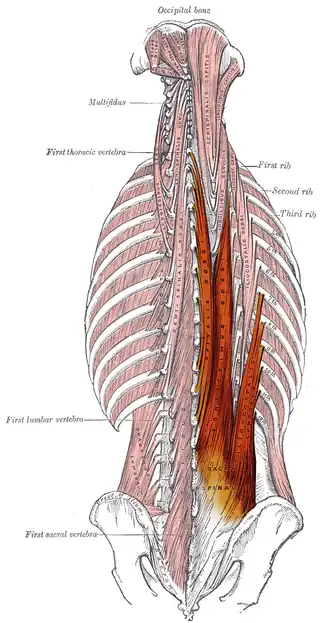

Erector spinae muscles

The erector spinae muscle group | |

The erector spinae (/ɪˈrɛktər ˈspaɪni/ irr-EK-tər SPY-nee)[1] or spinal erectors is a set of muscles that straighten and rotate the back. The spinal erectors work together with the glutes (gluteus maximus, gluteus medius and gluteus minimus) to maintain stable posture standing or sitting.

Structure

The erector spinae is not just one muscle, but a group of muscles and tendons which run more or less the length of the spine on the left and the right, from the sacrum, or sacral region, and hips to the base of the skull. They are also known as the sacrospinalis group of muscles. These muscles lie on either side of the spinous processes of the vertebrae and extend throughout the lumbar, thoracic, and cervical regions. The erector spinae is covered in the lumbar and thoracic regions by the thoracolumbar fascia, and in the cervical region by the nuchal ligament.

This large muscular and tendinous mass varies in size and structure at different parts of the vertebral column. In the sacral region, it is narrow and pointed, and at its origin chiefly tendinous in structure. In the lumbar region, it is larger, and forms a thick fleshy mass. Further up, it is subdivided into three columns. They gradually diminish in size as they ascend to be inserted into the vertebrae and ribs.

The erector spinae is attached to the medial crest of the sacrum (a slightly raised feature of the sacrum closer towards the midline of the body as opposed to the "lateral" crest which is further away from the midline of the body), to the spinous processes of the lumbar, and the eleventh and twelfth thoracic vertebrae and the supraspinous ligament, to the back part of the inner lip of the iliac crests (the top border of the hips), and to the lateral crests of the sacrum, where it blends with the sacrotuberous and posterior sacroiliac ligaments.

Some of its fibers are continuous with the fibers of origin of the gluteus maximus.

The muscular fibers form a large fleshy mass that splits, in the upper lumbar region, into three columns, viz., a lateral (iliocostalis), an intermediate (longissimus), and a medial (spinalis). Each of these consists of three parts, inferior to superior, as follows: